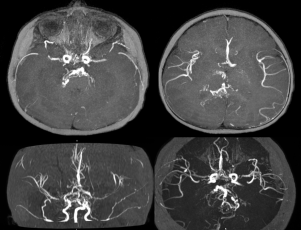

- l’IRM : elle montre les lésions ischémiques et hémorragiques, la vascularisation de suppléance au niveau diencéphalique

- l’angiographie des 6 axes : elle est nécessaire en pré-opératoire, pour étudier les les anastomoses extra-intra-crâniennes existantes et à respecter, rechercher des anévrysmes